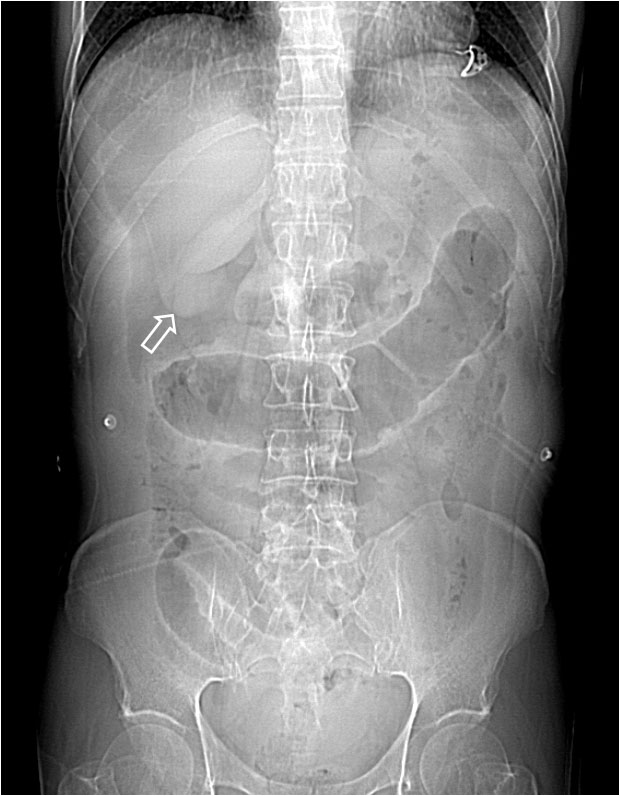

SIGNO DEL LIGAMENTO TERES

La demostración del segmento extrahepático del ligamento teres en la radiografía simple de abdomen, es un signo de neumoperitoneo moderado o masivo. El ligamento se ve como una banda con densidad de partes blandas que cruza el cuadrante superior derecho desde el borde inferior hepático hasta la región umbilical (flechas). Otras veces sólo es visible el margen inferolateral y, en vez de una banda, se ve una interfase bien delimitada.

Localización del ligamento teres (flecha), visible por la presencia de neumoperitoneo. Es visible también el Signo de Rigler.